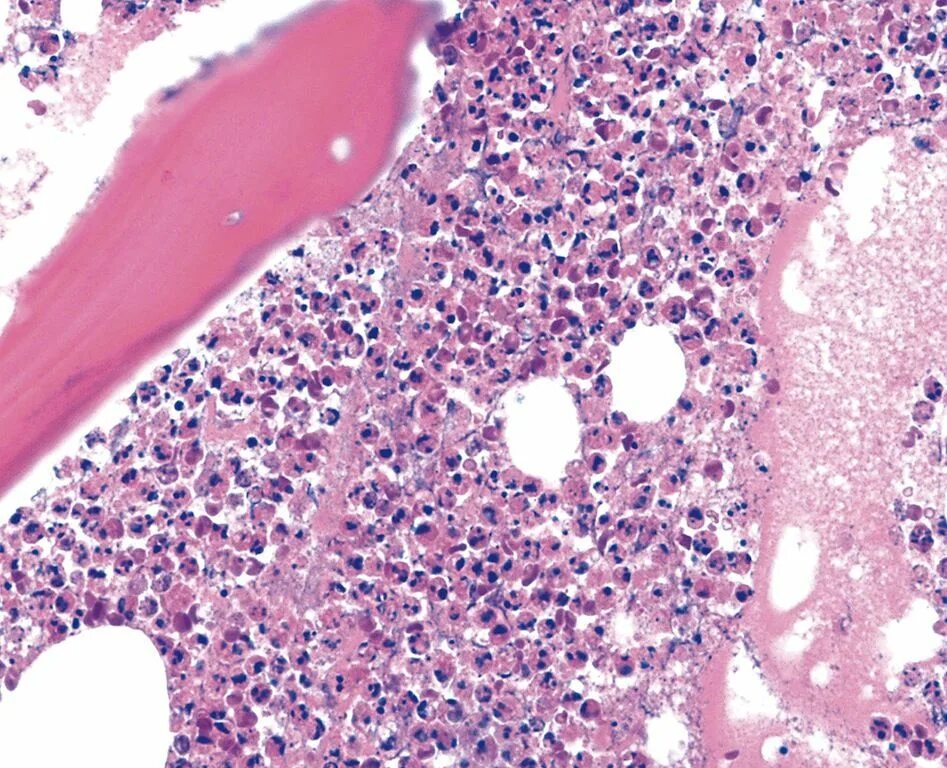

Метастазы в костном мозге